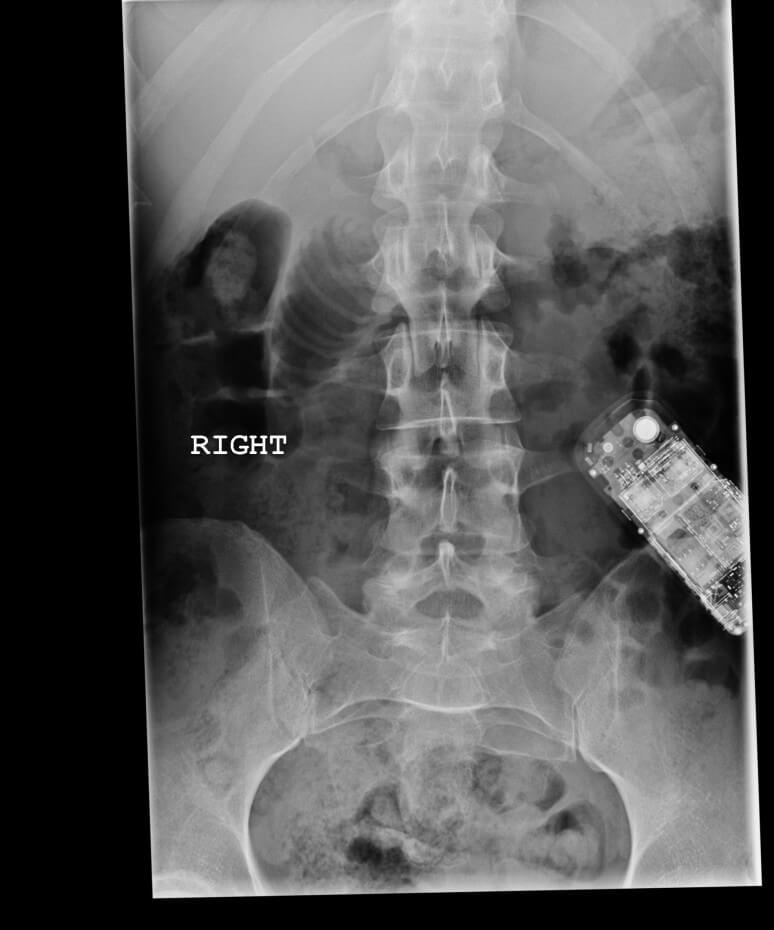

I will be the film composer for Rebecca Doppelt’s next film Bugbaby. I was on set today to get a head start by observing her directing, which was fun. I crashed my motorcycle on the way home, which was not. I was hospitalized with a serious concussion and I lost 24 hours of my memory, but I’m okay and the film is going to be great.